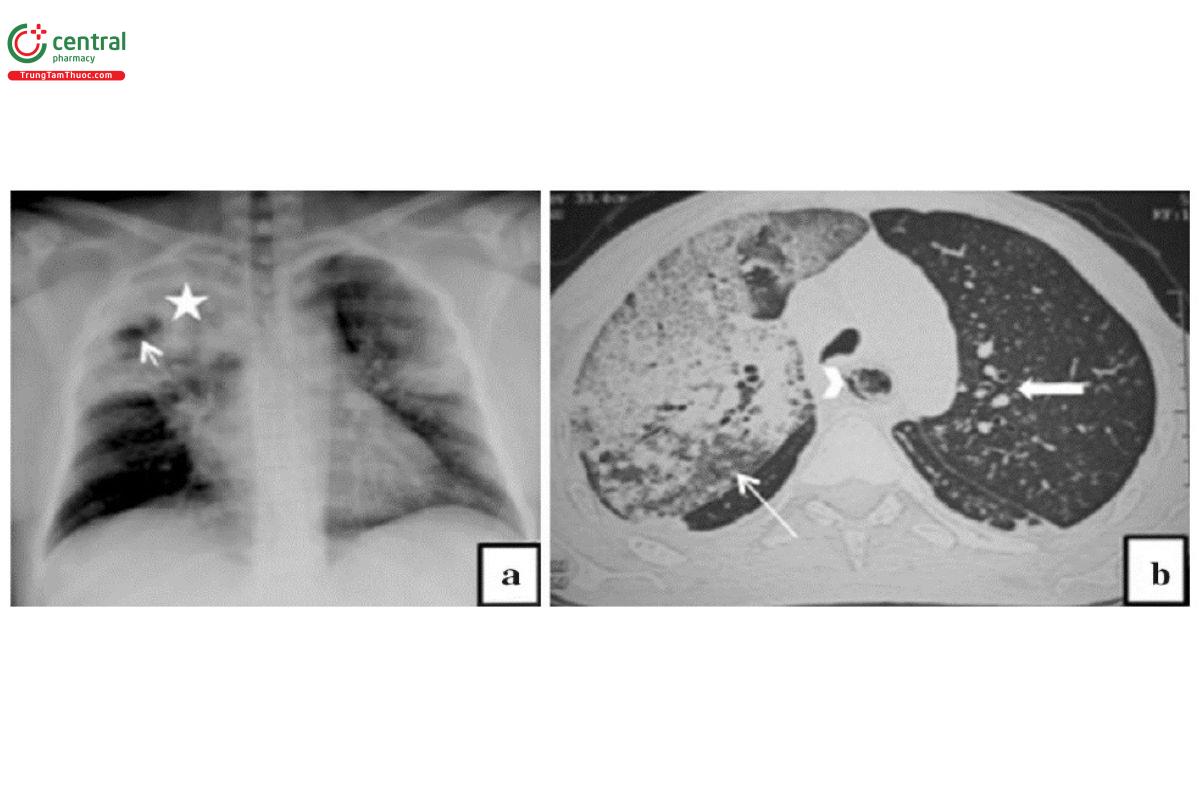

Viêm phổi do Streptococcus pneumoniae: Hình ảnh tổn thương là viêm phổi phế nang/thùy, thường có hình ảnh phế quản hơi, không thay đổi kích thước vùng phổi đông đặc và không có hang. Thùy dưới thường gặp nhiều hơn và có thể xuất hiện ở nhiều thùy. Tổn thương hai bên gặp ở khoảng một nửa số bệnh nhân.

Chú thích: a) Hình ảnh đông đặc (dấu sao) ở thùy trên bên trái với dấu hiệu phế quản hơi (mũi tên đen). b) Hình ảnh đông đặc thùy dưới bên phải (dấu sao) trên CT. c) Hình ảnh đông đặc thùy và dấu hiệu phế quản hơi (mũi tên đen).